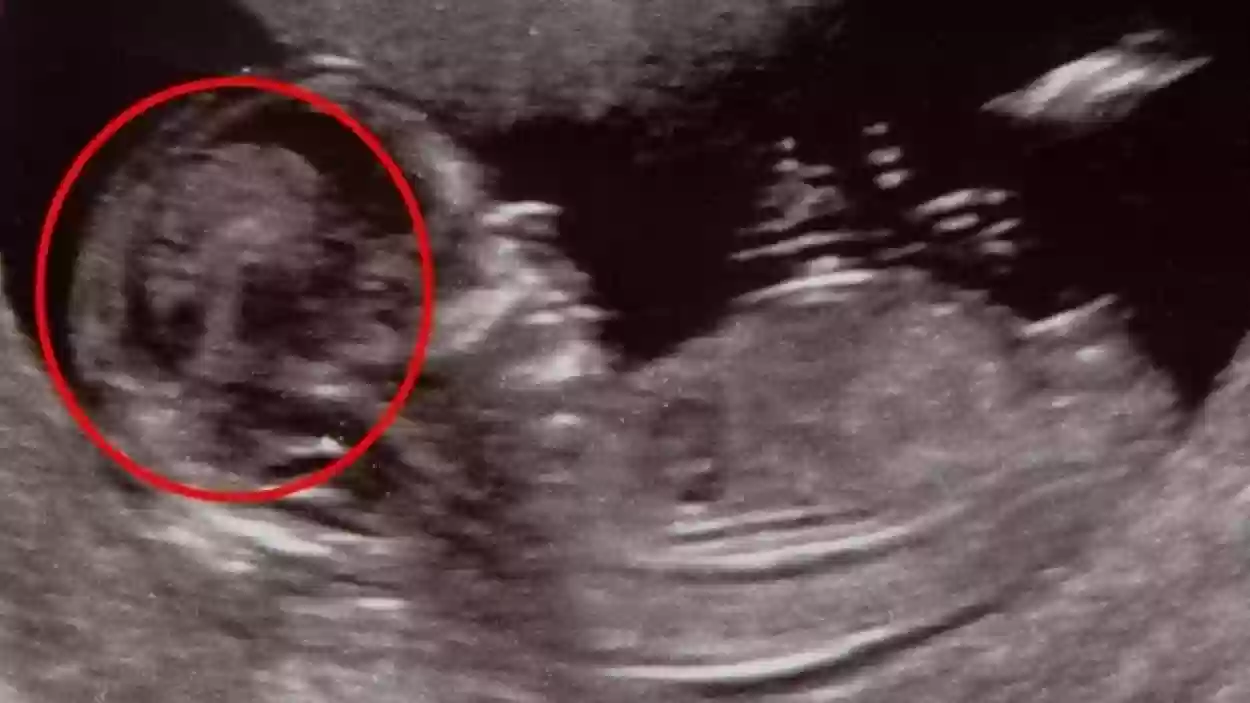

اعرفي الحقيقة | هل البنت تبان في بداية الشهر الرابع وهل تغلق رجليها في السونار؟